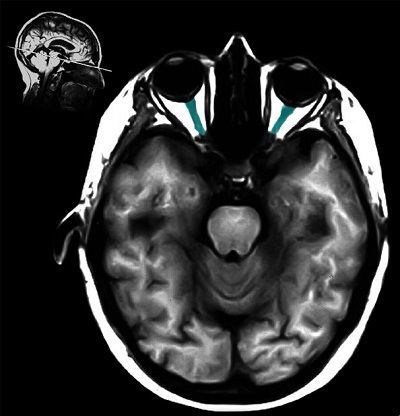

Question 4

Question

¿Qué estructura esta señalada?

Image:

d65befd4-d0e3-4035-b228-39123a4ee8d0 (image/jpeg)

Answer

Globulo Ocular

N. Optico

M. Ciliar

M. Recto